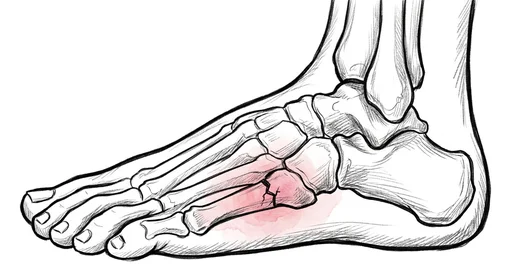

Foot & Ankle Exercise Guide

Choose your condition below to get started with exercises and stretches designed by Dr. Patish.

Pick your condition below, and you'll find your personalized exercise program — with medical illustrations, step-by-step instructions at three intensity levels, and clear guidance on when to call our office. Every protocol here is the same one Dr. Patish prescribes to patients in the clinic.

Forefoot & Toes

Fractures